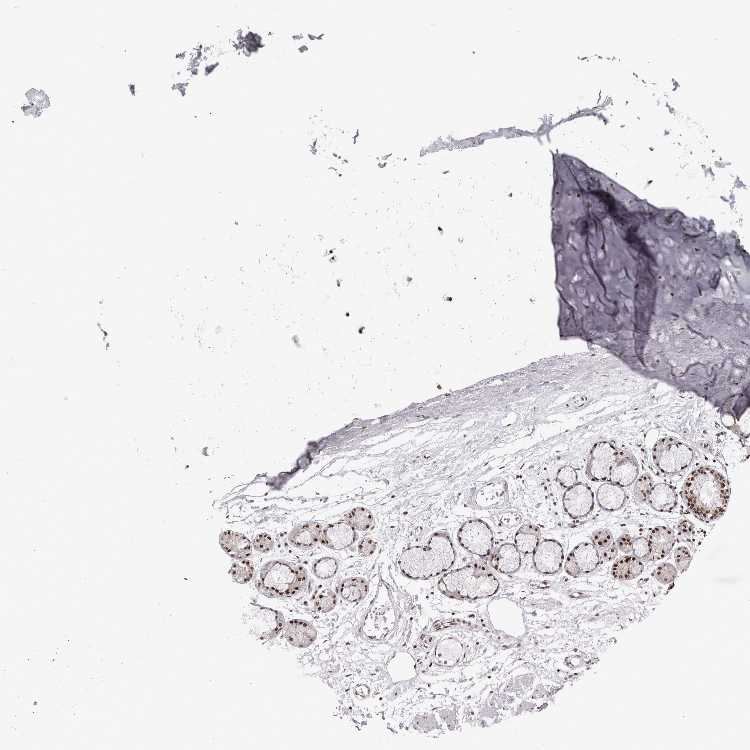

SOFT TISSUE 1 - Antibody stainingi

Antibody staining in the annotated cell types in the current human tissue is reported as not detected, low, medium, or high, based on conventional immunohistochemistry profiling in selected tissues. This score is based on the combination of the staining intensity and fraction of stained cells.

Each image is clickable and will lead to virtual microscopy that enables deeper exploration of all samples and also displays staining intensity scores, fraction scores and subcellular localization as well as patient and tissue information for each sample.

Antibody HPA024331

Chondrocytes High

Fibroblasts High

Peripheral nerve High